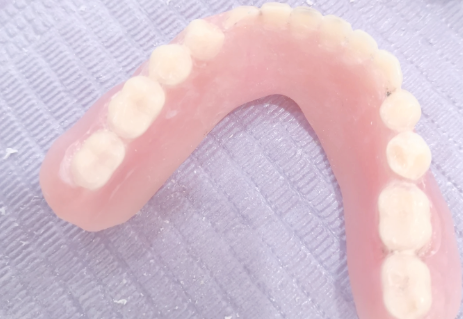

16. 活动假牙:800 - 3000元

17. 固定假牙:1500 - 5000元